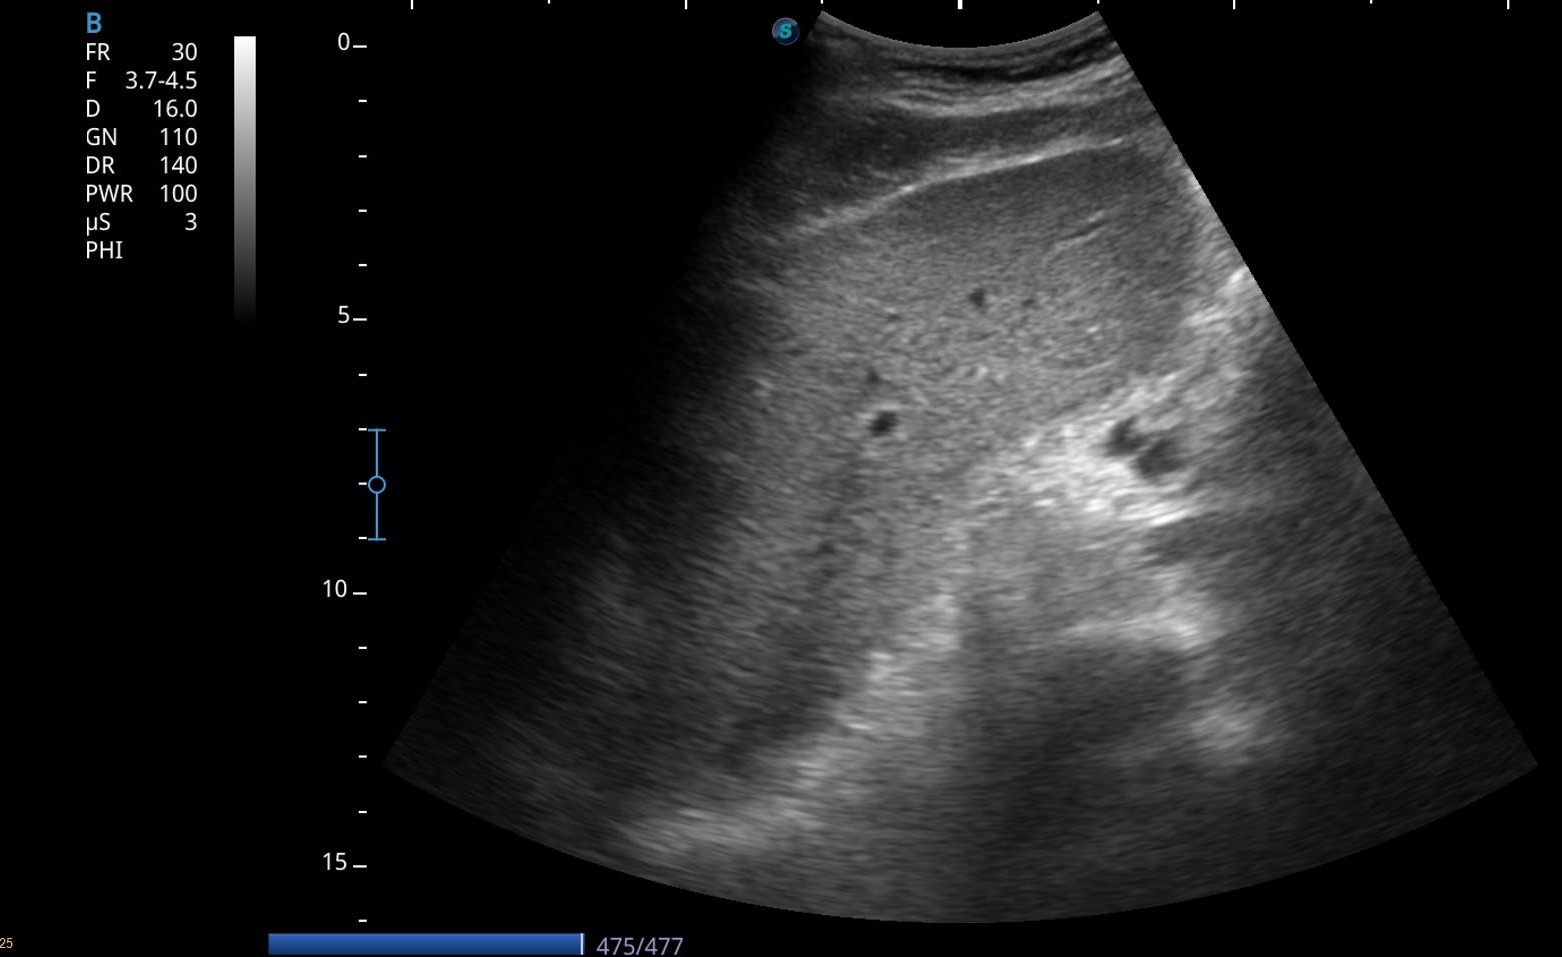

Debido a la alteración analítica se realiza una ecografía abdominal en la consulta.

Hallazgos ecográficos

Eco abdomen: Hígado de tamaño normal, nódulo en LHI de 2 cm y una gran masa heterogénea mal definida de unos 10 cm.

Resto dentro de la normalidad.